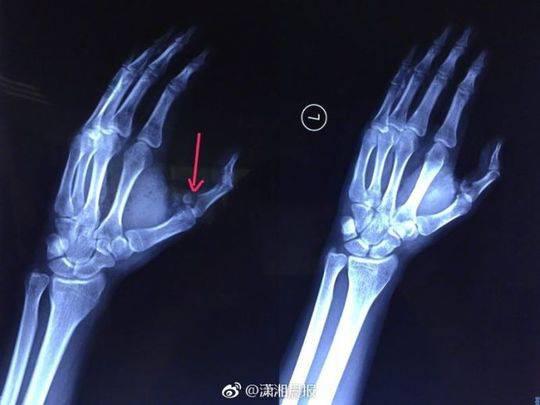

劇烈的疼痛讓小袁發出慘叫,家人聞訊趕來一看,只見他的傷口血流不止,受傷的左手也動彈不得,隨即將他送往湖南省人民醫院急診一科就診,醫生為其傷口進行了緊急處理。X 光檢查發現,小袁的左手拇指近節指骨骨折,需進行手術固定,于是將他收入創傷骨病科病房。

當晚10點,該院創傷骨病科何畔副主任醫師等為小袁施行 “ 左手清創探查、左拇指近節指骨骨折切開復位 + 克氏針內固定術 ”,手術歷時 2小時順利完成。術后,小袁的左手需采用石膏固定4~6周。